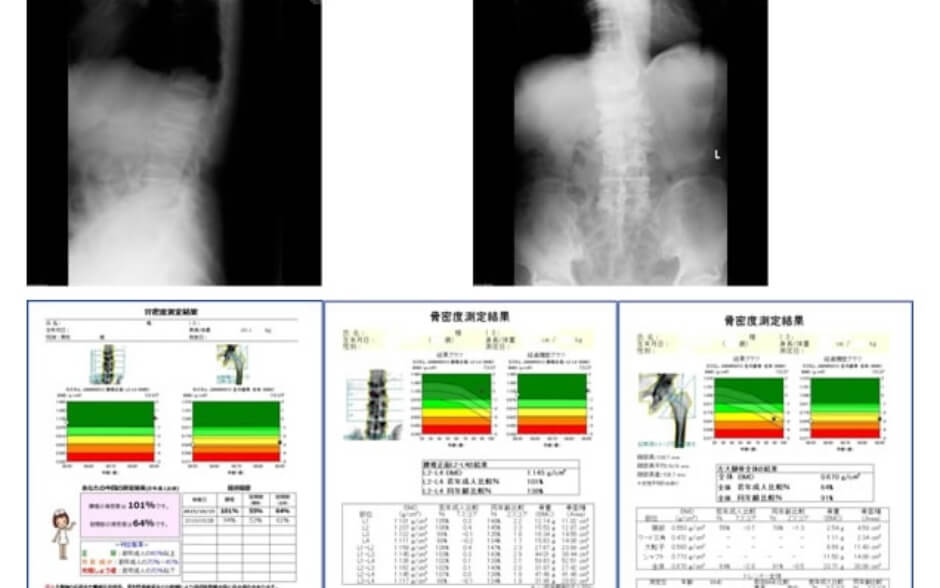

トモシンセシス

3Dマンモグラフィ

トモシンセシスでは3Dマンモグラフィ撮影が可能です。従来のマンモグラフィ撮影は2Dであったのでより多い情報により診断制度の向上が期待されます。また、3Dマンモグラフィでは1回の撮影で連続的にX線を照射し、奥行き方向(3次元的)に細かくスライスした断層画像が複数枚得られます。